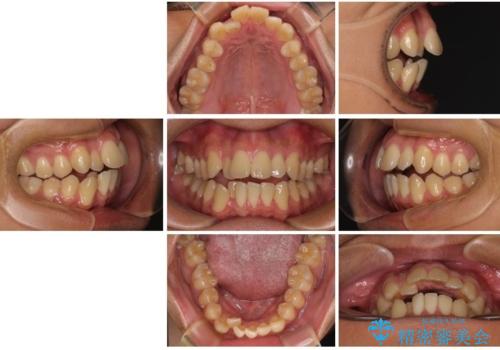

- 前歯のデコボコ(叢生)と、少し前に出た口元を気にされて来院された患者さまです。

診査の結果、上下顎ともに歯が並ぶスペースが不足しており、上下の前歯が噛み合わない**オープンバイト(開咬)**の状態でした。

歯をすべて並べようとすると口元がさらに前に出てしまうため、上下左右の第一小臼歯を抜歯してスペースを確保し、デコボコと突出感の両方を改善する治療計画を立てました。